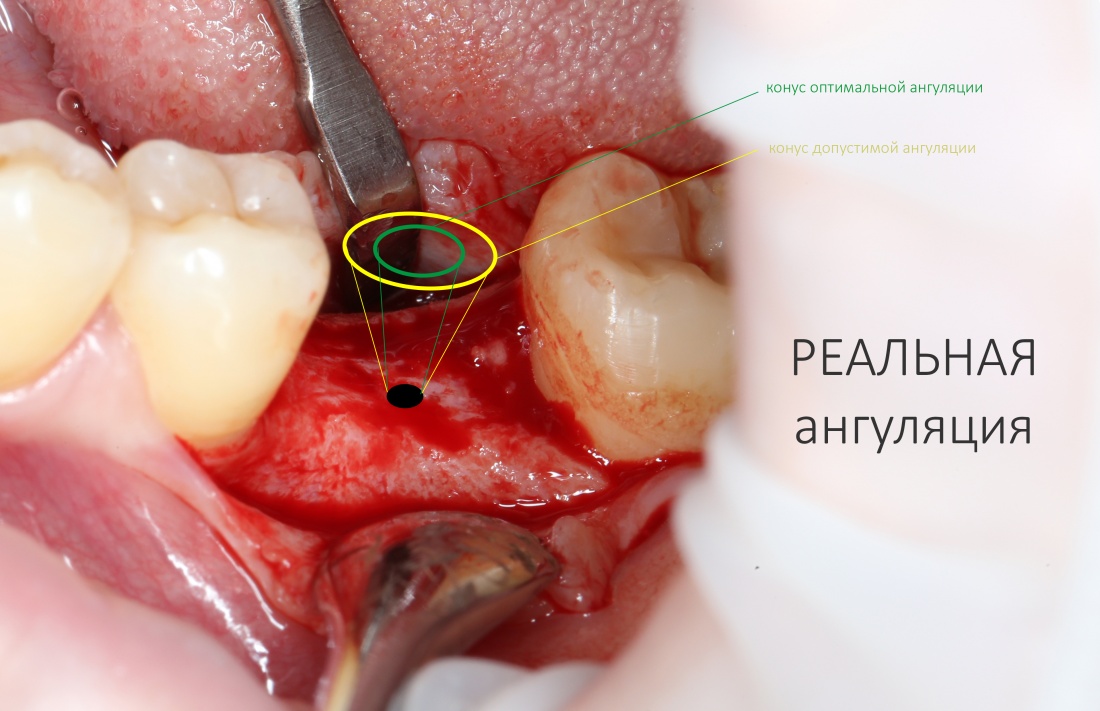

Одна милая дама обратилась в стоматологическую клинику с просьбой восстановить разрушенный передний зуб. После обследования выяснилось, что зуб придётся удалить, и ей предложили удаление с одномоментной имплантацией и т. н. «немедленной нагрузкой» — коронкой. И вот, доктор удалил зуб, пытался установить имплантат, но торк, усилие при установке, на его взгляд, оказался недостаточным для фиксации коронки. И он вкручивает имплантат глубже и круче, «штоб хорошо держался». Установил. Ортопед, увидевший такую установку, пришел в ужас, но приказ есть приказ — и он попытался сделать на этот имплантат коронку. Смотрите внимательно:

Два последних кадра сделаны во время удаления этого имплантата, и они дают наглядное представление о причине такого «концептуального» подхода к протезированию. И объясняют, почему мы вынуждены всё это переделывать.

На мой взгляд, наиболее сложным является позиционирование по глубине погружения во время операции немедленной имплантации, поскольку иногда для достижения достаточной первичной стабильности, очень хочется «вкрутить» имплантат поглубже. И это очень распространенная ошибка. Собственно, так и произошло в случае, с которого я начал эту статью:

Чуть выше я уже говорил, что ангуляция может быть оптимальной, допустимой и критической. Последняя делает протезирование на таком импланте просто невозможным: